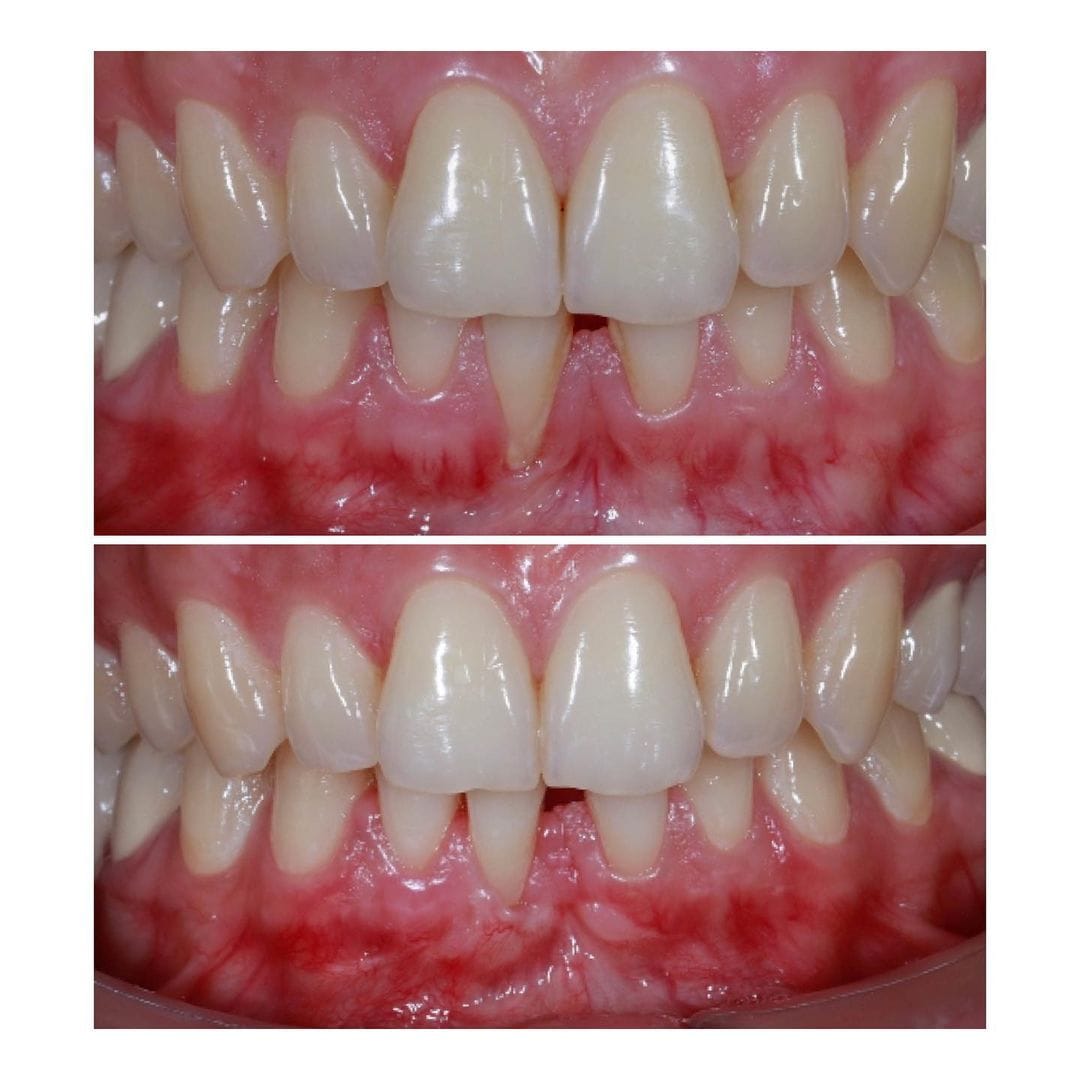

Çoxlu diş əti çəkilməsi olan xəstənin damağdan aldığımız yumuşaq toxuma ile tam qapadılması

Alt kəsici dişətinin çəkilməsi olan pasientin damaqdan diş əti parçası alaraq bərpası

Diş əti çəkilməsi olan xəstənin tunel əməliyyatı ilə çəkilmənin qapadılması